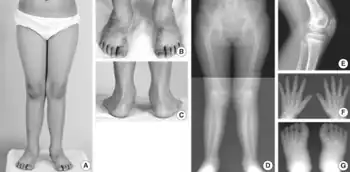

Autosomal recessive multiple epiphyseal dysplasia (ARMED), also called epiphyseal dysplasia, multiple, 4 (EDM4), multiple epiphyseal dysplasia with clubfoot or –with bilayered patellae,[1] is an autosomal recessive[2] congenital disorder affecting cartilage and bone development. The disorder has relatively mild signs and symptoms, including joint pain, scoliosis, and malformations of the hands, feet, and knees.[3]

Some affected individuals are born with an inward- and downward-turning foot (a clubfoot). An abnormality of the kneecap called a double-layered patella is also relatively common. Although some people with recessive multiple epiphyseal dysplasia have short stature as adults, most are of normal height. The incidence is unknown as many cases are not diagnosed due to mild symptoms.